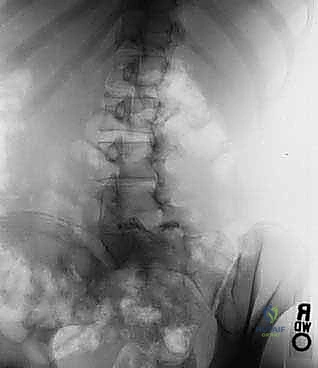

- الأشعة السينية الديناميكية (Dynamic X-rays): صور في وضعية الانحناء للأمام والخلف لتقييم مدى عدم استقرار الفقرات وحركتها غير الطبيعية.

- التصوير بالرنين المغناطيسي (MRI): هو المعيار الذهبي لرؤية الأنسجة الرخوة. يوضح بدقة متناهية حالة الأقراص الغضروفية، ومقدار الاختناق في القناة الشوكية، والضغط الواقع على جذور الأعصاب.

- التصوير المقطعي المحوسب (CT Scan): يقدم تفاصيل دقيقة للبنية العظمية، وهو ضروري جداً للتخطيط الجراحي وتحديد مسار المسامير (Pedicle Screws) في الجراحة.